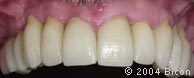

118. | 上颌的唇颊侧观。 |